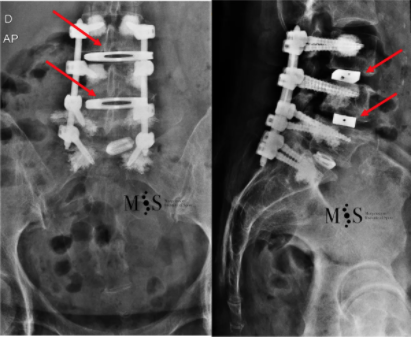

These images depict the post-operative correction of the scoliosis

after placement of two OLIF cages (marked by red arrows).